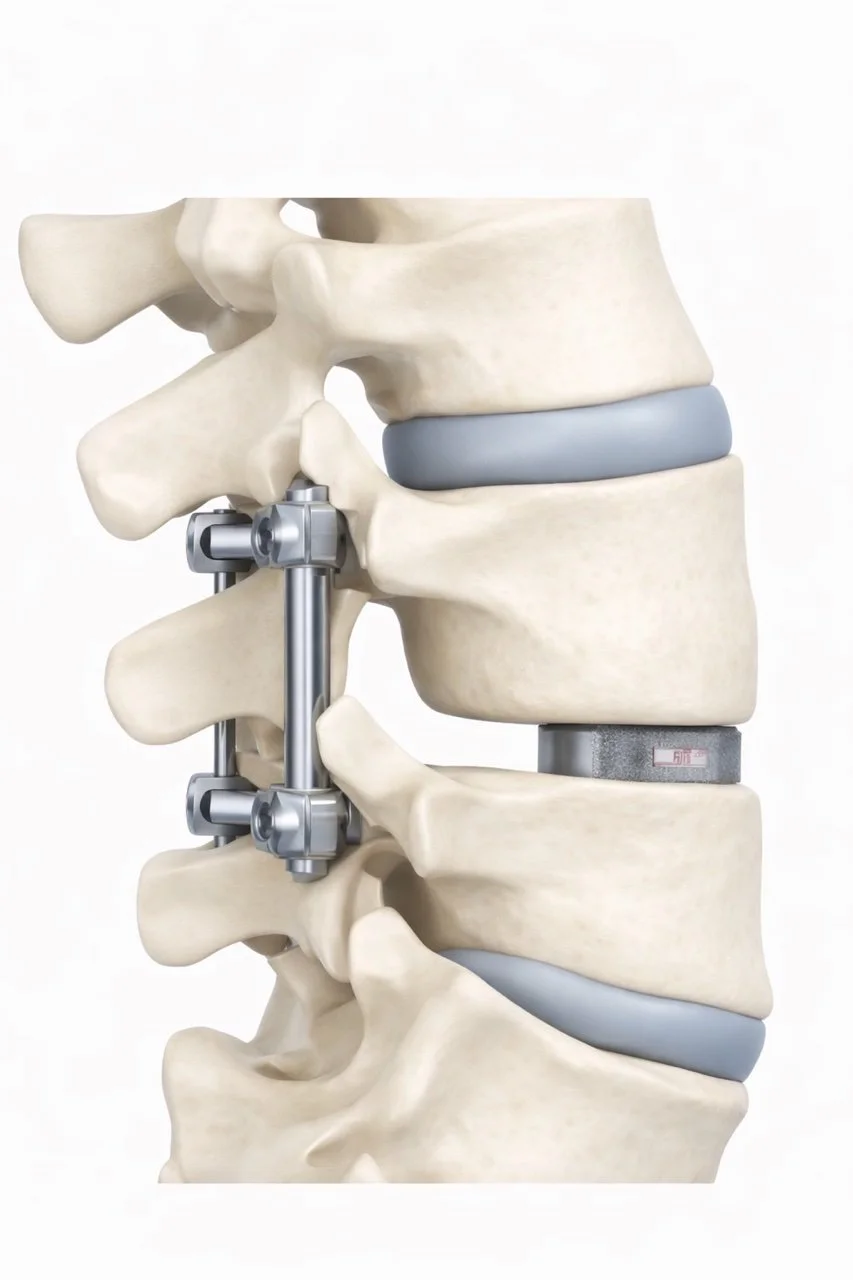

Surgery focuses on creating more space for the nerves.

The most common procedure is a lumbar decompression (laminectomy), which removes bone and tissue that are compressing the nerves.

In some cases, spinal fusion may also be recommended if instability is present.

A detailed anatomical model of a human spine showing vertebrae, intervertebral discs, and spinal hardware, possibly used for educational or medical purposes.

• It is a procedure that removes bone and tissue to relieve pressure on the nerves.

• Fusion is only needed if there is instability in the spine, or other factors such as severe arthritis or scoliosis.

• Many decompression procedures can be performed using minimally invasive techniques.